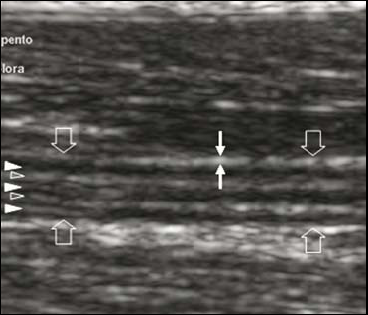

超声图像显示的前臂中1/3处正中神经长轴断面,频率5-12MHz。

正中神经是平行线样低回声区(白色箭头),神经束由束间神经外膜平行的带状强回声所分隔(空心箭头)。注意:神经外膜(白色箭头)